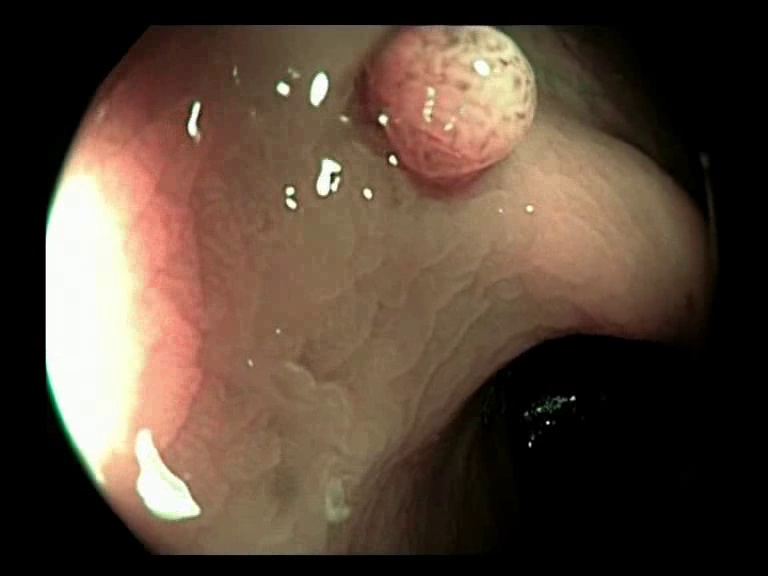

Figure 3: Key-frames obtained by our method and their corresponding depth maps. The polyp is visible from different viewing angles in these selected frames.

The selected key-frames are finally used to reconstruct the 3D surface of the polyp. We have used Facebook’s 3D image GUI to view the reconstructed polyp surface, the link to the video is shown here: https://youtu.be/PJKfk0Mqu2I\href https://youtu.be/PJKfk0Mqu2I. 3D visualization of a polyp helps in surgeries involving the removal of the polyp from its root. This gives better visualization of polyps for diagnosis. Fig. 3 shows some of the results of key-frame extraction and the corresponding depth maps. No publicly available datasets or methods using them that predict depth maps from endoscopic frames exist. Thus, a comparison between different methods for predicting depth from endoscopic images couldn’t be performed.